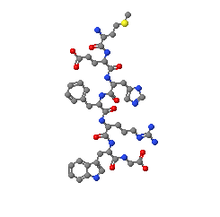

| تركب الهرمون المنشظ للغدة الكظرية | |